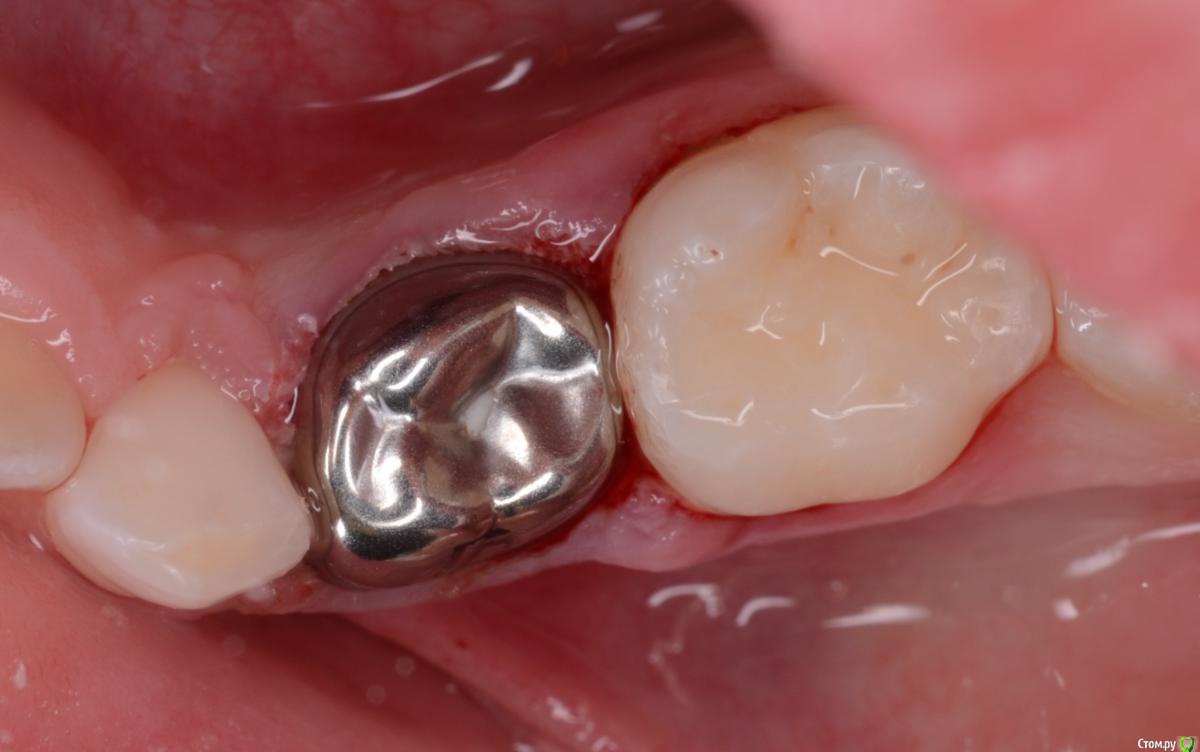

CRAZYDUCK Опубликовано 7 июня, 2018 Автор Поделиться Опубликовано 7 июня, 2018 Восстановление десны после фиксации коронки происходит примерно за неделю . Ниже фото в день фиксации и через 10 дней . 1 Ссылка на комментарий

crown Опубликовано 8 июня, 2018 Поделиться Опубликовано 8 июня, 2018 Восстановление десны после фиксации коронки происходит примерно за неделю . Ниже фото в день фиксации и через 10 дней .Коронка вне прикуса. Как вам идея снимать слепки и отдавать техникам для изготовления штамповок? Ссылка на комментарий

CRAZYDUCK Опубликовано 8 июня, 2018 Автор Поделиться Опубликовано 8 июня, 2018 Коронка вне прикуса. Как вам идея снимать слепки и отдавать техникам для изготовления штамповок? ну и что , что вне прикуса , тремы тоже бывают , это же стандартные коронки . Насчет техника - нет , я за одно посещение . Бывает завышает немного , но за неделю все нормализуется . Проблем с суставом не будет . Ссылка на комментарий

CRAZYDUCK Опубликовано 9 июня, 2018 Автор Поделиться Опубликовано 9 июня, 2018 Коронка вне прикуса. Как вам идея снимать слепки и отдавать техникам для изготовления штамповок? я пробовала с техником - нет гарантии , что коронка будет идеально сидеть ( ну у меня так было ), а анестезию два раза делать и два визита нужно. Не стоит придираться сильно к коронкам. Я сначала тоже снимки смотрела , по высоте прикуса , ко всему придиралась и волновалась . Но сейчас я понимаю , что некоторые погрешности ( точнее неидеальности ) в коронках не могут навредить . Это же не индивидуальные все-таки конструкции. В общем я за стандартные коронки двумя руками. Ссылка на комментарий